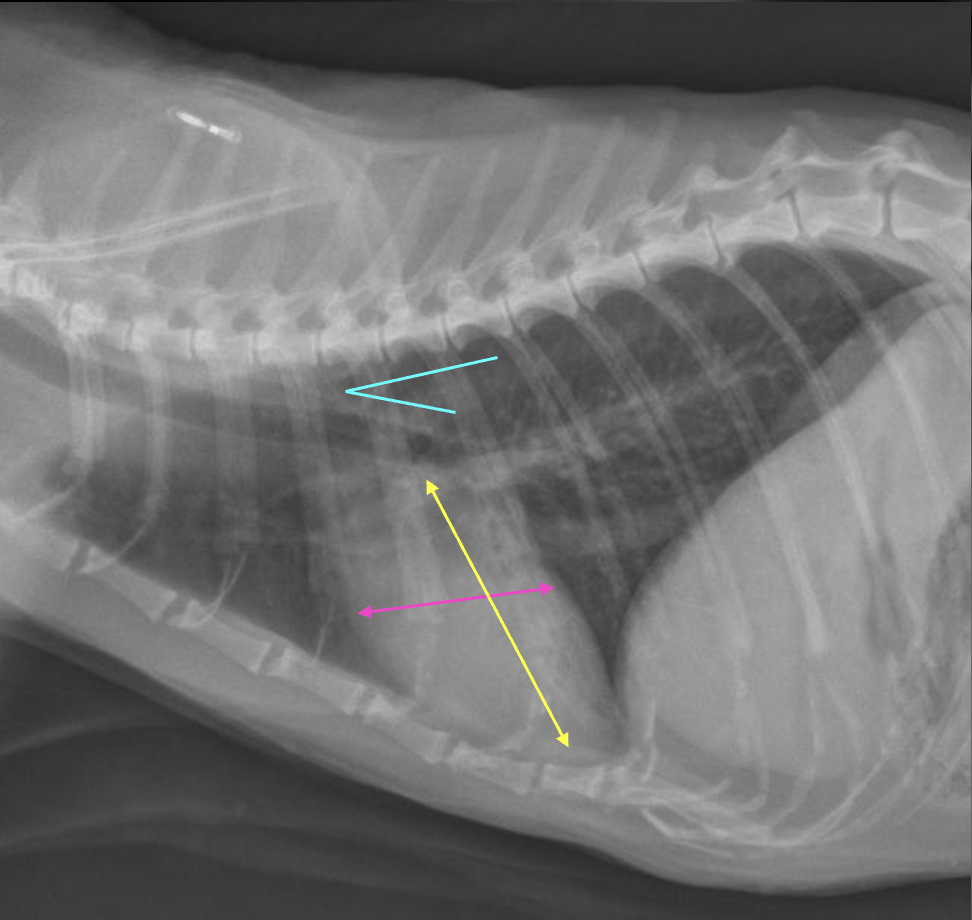

What are the normal characteristics of the feline heart in a lateral view?

A

-heart height is ~ 2/3 of the diameter from dorsal to ventral chest (yellow)

-heart is 2 to 2.5 intercostal spaces wide (pink)

-trachea deviates from spine (blue)